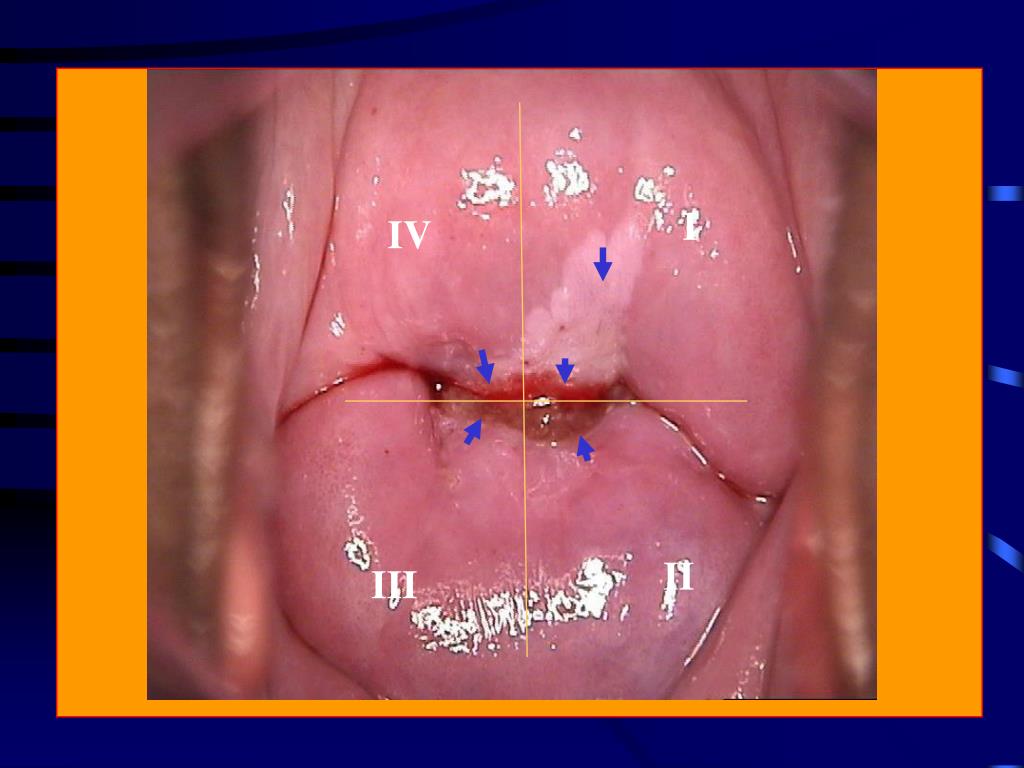

4. I IV II III